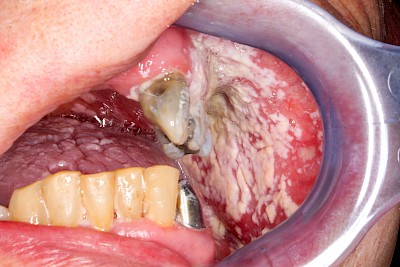

Borken

Borken sind verkrusteter Schleim und ebenfalls ein Zeichen für Mundtrockenheit. Gerade im Bereich der Prothesenauflageflächen können Borken auch mit Haftcremeresten verwechselt werden oder mit diesen vermengt sein. In jedem Fall sollte zunächst die Pflege der Mundschleimhäute und Zahnprothesenpflege intensiviert werden.

Beispiele4 Bilder